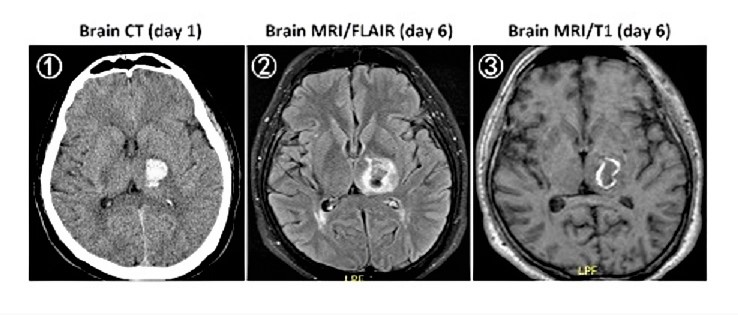

【112-2 醫學(四) 第46題】49歲男性平常有高血壓,因突發性右側肢體無力及麻木而就診,就診當天的無顯影劑腦部電腦斷層(non-contrast CT)檢查結果如下圖①,5天後的腦部磁振造影(MRI)檢查結果如下圖②(Fluid attenuated inversion recovery, FLAIR)及圖③無施打顯影劑之T1影像。下列何者最有可能是此病人的診斷?

本題的解題核心在於判讀影像的演變。病人突發性神經學症狀,加上第一天的腦部電腦斷層(CT)顯示急性高密度病灶,這是急性腦出血的典型表現。後續的磁振造影(MRI)則呈現出血病灶的演變過程。